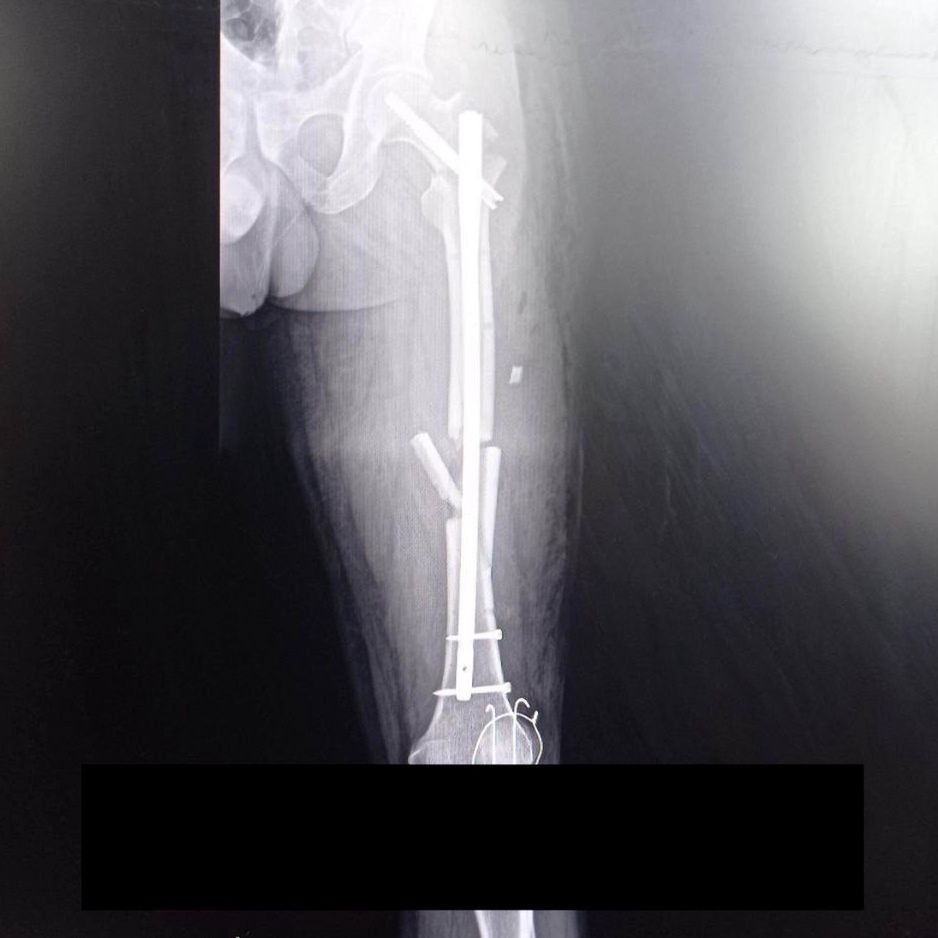

Efekty wypadku były bolesne: rany szarpane obu rąk, złamany palec, cztery złamania w lewej nodze, uszkodzenie stawu kolanowego i dwa złamania kości. Wirtualna Polska posiada zdjęcia rentgenowskie Oleha.

• Tak wygląda noga Oleha po wypadku - Wirtualna Polska posiada zdjęcia rentgenowskie i jego dokumentacje medyczną

[1/2] Tak wygląda noga Oleha po wypadku - Wirtualna Polska posiada zdjęcia rentgenowskie i jego dokumentacje medyczną Źródło zdjęć: Wirtualna Polska | Wirtualna Polska

Zniszczone auto miało zmiażdżony przód, wylądowało w rowie, a sam kierowca wypadł z pojazdu. W efekcie odniósł liczne obrażenia, w tym złamania. Dotarliśmy do jego dokumentacji medycznej i zdjęć rentgenowskich. Do dziś skarży się na uporczywy ból, ma problemy z chodzeniem, porusza się o kulach i nie może samodzielnie funkcjonować.